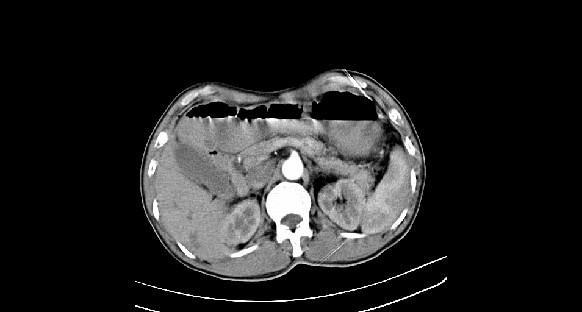

男性,70岁,体检b超发现左肾占位,请各位战友发表一下观点

左肾有两个病灶,且较大的病灶内可见点状钙化灶,增强扫描边缘也是呈渐进性强化,中央部分未见明显强化